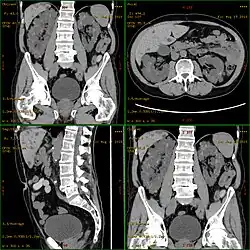

Autosomal dominant

CT scan showing autosomal dominant polycystic kidney disease

Polycystic kidney disease can be ascertained via a CT scan of abdomen, as well as an MRI and ultrasound of the same area.[23] A physical exam/test can reveal enlarged liver, heart murmurs and elevated blood pressure.[1]